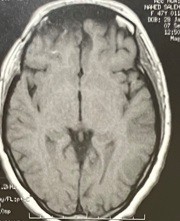

ورم بالفص الامامي بقاع الجمجمة

صورة فحص رنين مغناطيسي بالصبغة علي المخ لورم سحائي بالحجرة الامامية بقاع الجمجمة  قبل وبعد اجراء جراحة ميكروسكوبية  ناجحة لاستئصالة .